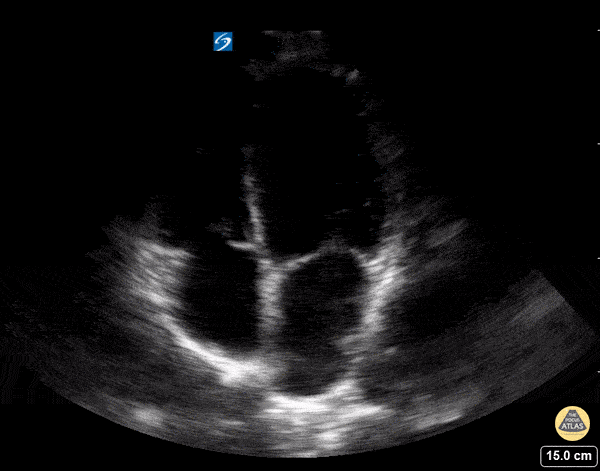

Parasternal Long Axis

• ANATOMIC LANDMARK: left sternal border, 3-4th interspace

• Probe marker to the right shoulder

• SONOGRAPHIC LANDMARK: HEART

• Identify:

• LV, RV, LA, MV, AV

• Pericardium +/- Pericardial/pleural fluid